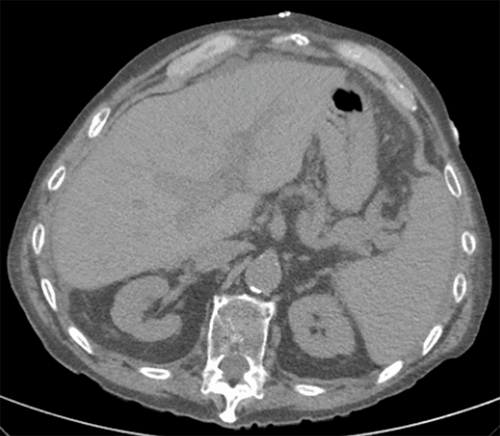

A postoperative CT scan of the abdomen and pelvis was obtained for concern of deeper infection after the patient developed incisional erythema that ruled out an abdominal wall or intraabdominal abscess and revealed no hematoma around the liver (Figure 5). The patient's postoperative course was complicated by an incisional infection that required a partial opening of the surgical wound. He was subsequently discharged on POD 18 to subacute rehab.

Figure 5. CT Scan of Abdomen and Pelvis Obtained on POD 7 Reveals No Perihepatic Hematoma. Published with Permission